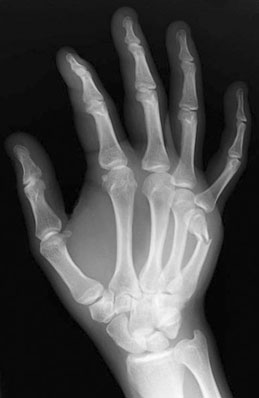

A Boxer's fracture is a break of the metacarpal of the little or ring finger. The metacarpals are the long bones in the hand that connect the fingers to the wrist. A boxer's fracture refers to a break at the end of the bone nearest to the knuckle, which is called a metacarpal neck.